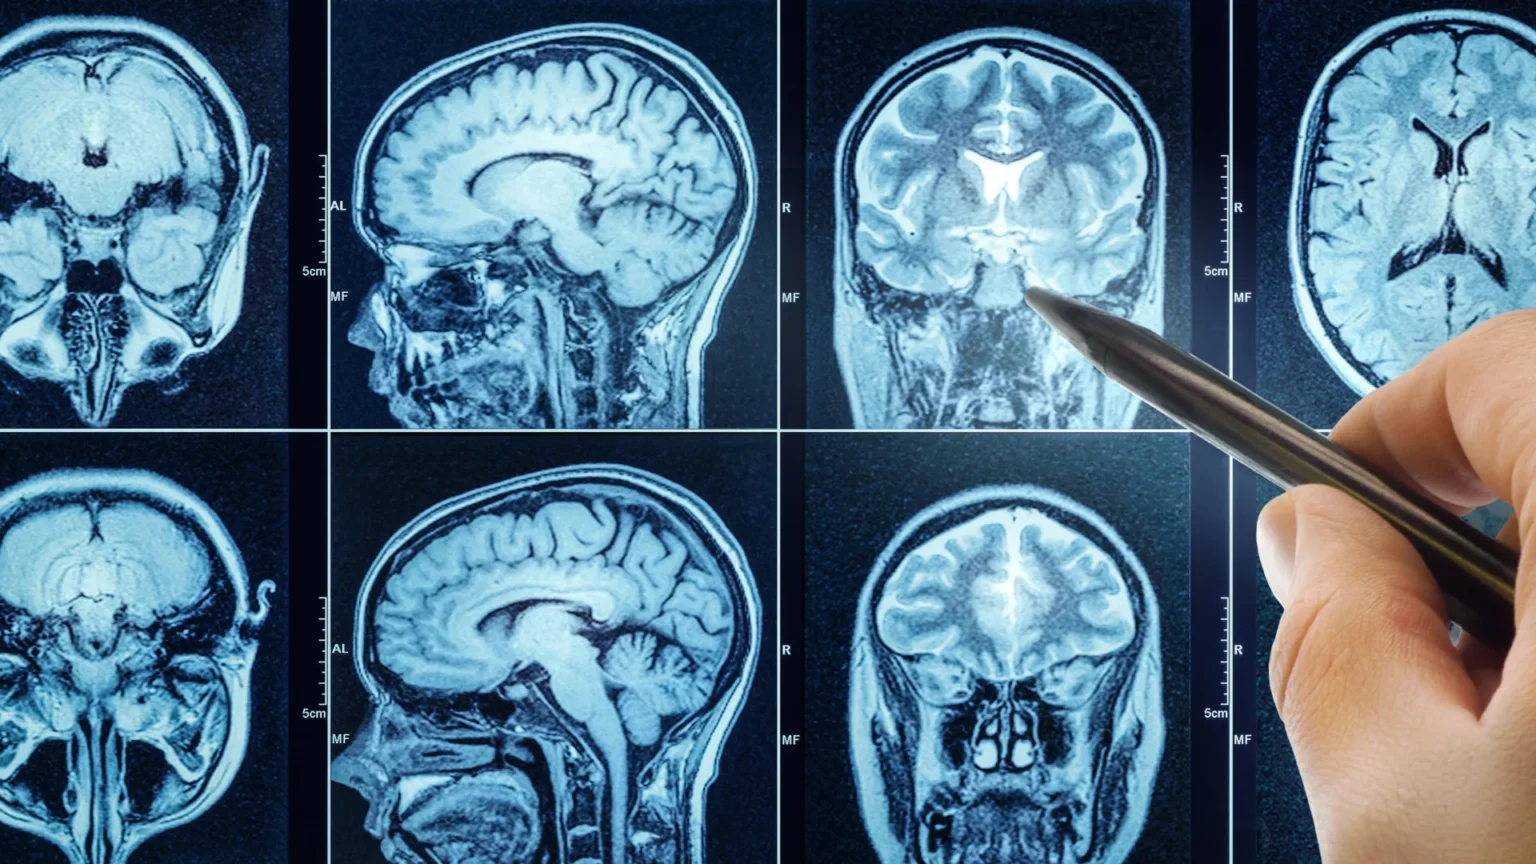

Όταν το μυαλό «κουράζεται»: Τι δείχνει η μαγνητική απεικόνιση

Η μελέτη, που δημοσιεύθηκε στις 11 Ιουνίου στο Journal of Neuroscience και χρηματοδοτήθηκε από τα National Institutes of Health (NIH), χρησιμοποίησε λειτουργική μαγνητική τομογραφία (fMRI) σε 28 υγιείς εθελοντές, ηλικίας 21 έως 29 ετών (18 γυναίκες και 10 άνδρες). Οι συμμετέχοντες υποβλήθηκαν αρχικά σε μια βασική εγκεφαλική απεικόνιση και στη συνέχεια εκτέλεσαν απαιτητικές δοκιμασίες εργαζόμενης μνήμης, κατά τη διάρκεια των οποίων καταγράφονταν οι εγκεφαλικές λειτουργίες τους.

Επιπλέον, σύμφωνα με τους επιστήμονες, η εν λόγω μελέτη ίσως αποτελέσει ένα εργαλείο για να αξιολογούμε αντικειμενικά την ψυχική κόπωση (και όχι μόνο με βάση το πώς λέει κάποιος ότι νιώθει) και αυτό θα γίνει συνδυάζοντας: την εγκεφαλική απεικόνιση (όπως fMRI) αλλά και τα πειράματα λήψης αποφάσεων, που δείχνουν πώς αλλάζει η συμπεριφορά όταν κάποιος νιώθει πνευματικά κουρασμένος